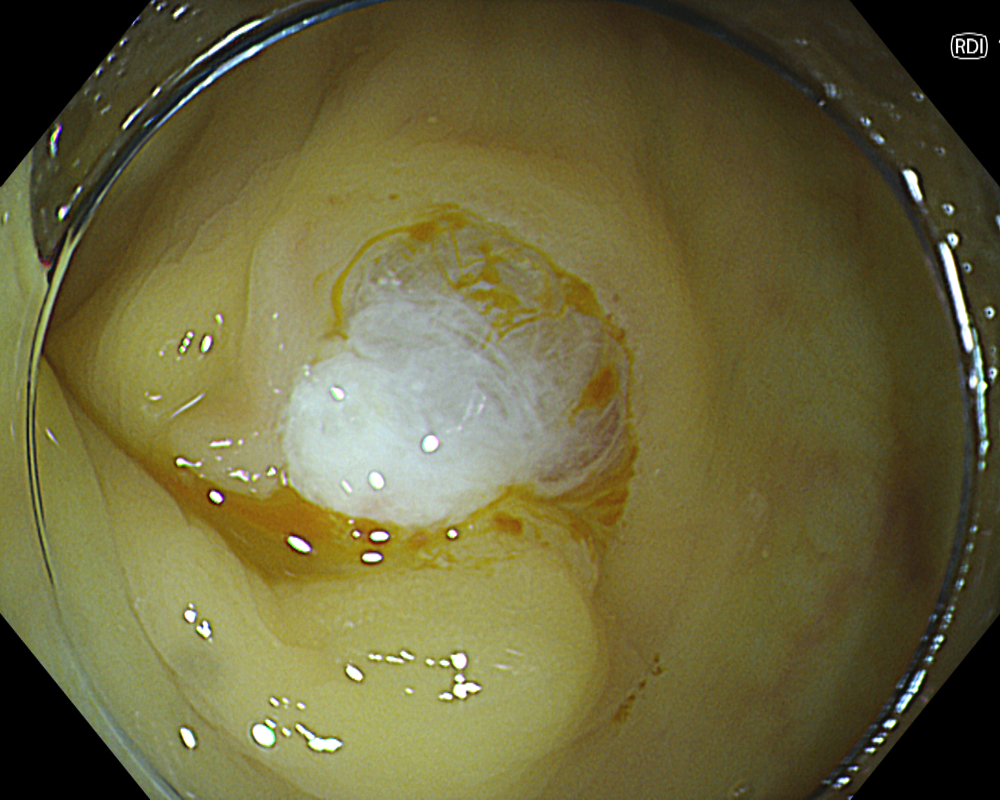

The points to note immediately after CSP are bleeding and residual tissue. Since CSP does not involve electrocautery, there is no so-called “burning effect.” Therefore, when capturing the lesion with the snare, it is important to include a margin of surrounding non-neoplastic mucosa. After CSP, re- examine the mucosal defect margin using NBI + Near focus to check for any residual tissue. Again, the EDOF function makes focusing and magnified observation significantly easier here.

While pulsatile or arterial bleeding is rare after CSP, minor oozing is almost always present. Applying the water jet to the post-CSP mucosal defect helps achieve a tamponade state for pressure-based hemostasis. Red Dichromatic Imaging (RDI) is a wavelength selection technology that enhances the visibility of deep vessels and bleeding points, making it useful for identifying bleeding sites and evaluating hemostasis. Even when a bleeding point is difficult to confirm, switching to RDI facilitates its identification, making hemostatic procedures and confirmation of successful hemostasis much easier and highly useful.